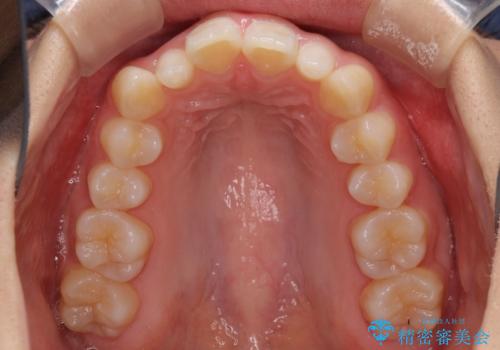

前歯のデコボコを治したい インビザラインによる矯正治療

- 前歯のデコボコ気になるとのことで来院された患者様です。

上下顎ともに歯列全体の後方移動とIPR(歯と歯の間を削る)によってデコボコが解消するように設計し、インビザラインにより治療を行うこととしました。

上顎左右前歯に矮小歯があるため、上顎の奥歯は下顎に対して相対的に前方に位置することになりました。

それでも奥歯の咬みにくさはなく、患者様には大変満足していただきました。